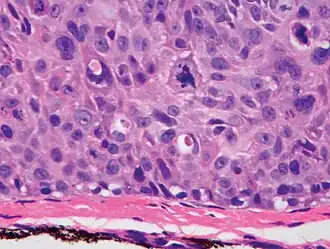

Histological characteristics

Histopathologically, the epidermis in cSCC in situ (Bowen's disease) will show hyperkeratosis and parakeratosis. There will also be marked acanthosis with elongation and thickening of the rete ridges. These changes will overly keratinocytic cells, which are often highly atypical and may have a more unusual appearance than invasive cSCC. The atypia spans the full thickness of the epidermis, with the keratinocytes demonstrating intense mitotic activity, pleomorphism, and greatly enlarged nuclei. They will also show a loss of maturity and polarity, giving the epidermis a disordered or "windblown" appearance.

Two types of multinucleated cells may be seen: the first will present as a multinucleated giant cell, and the second will appear as a dyskeratotic cell engulfed in the cytoplasm of a keratinocyte. Occasionally, cells of the upper epidermis will undergo vacuolization, demonstrating an abundant and strongly eosinophilic cytoplasm. There may be a mild to moderate lymphohistiocytic infiltrate detected in the upper dermis.[12]

Histopathology of squamous-cell carcinoma in situ (black arrow), compared to normal skin, showing marked atypia. -

Squamous-cell carcinoma in situ, showing prominent dyskeratosis and aberrant mitoses at all levels of the epidermis, along with marked parakeratosis.[12]